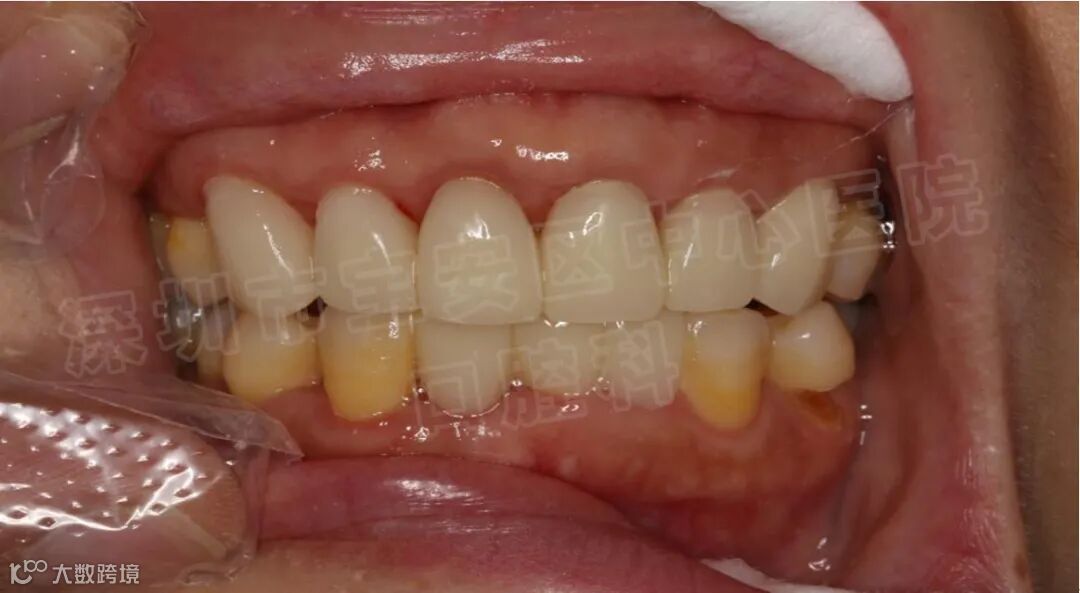

修复治疗

修复治疗成为牙周炎综合治疗的重要组成部分,牙周炎的修复治疗是在牙周基础治疗的基础上,通过修复学的方法来改善患牙的松动、移位及咀嚼无力等症状。牙周炎的修复治疗主要包括调牙合、正畸疗法和牙周夹板固定等。